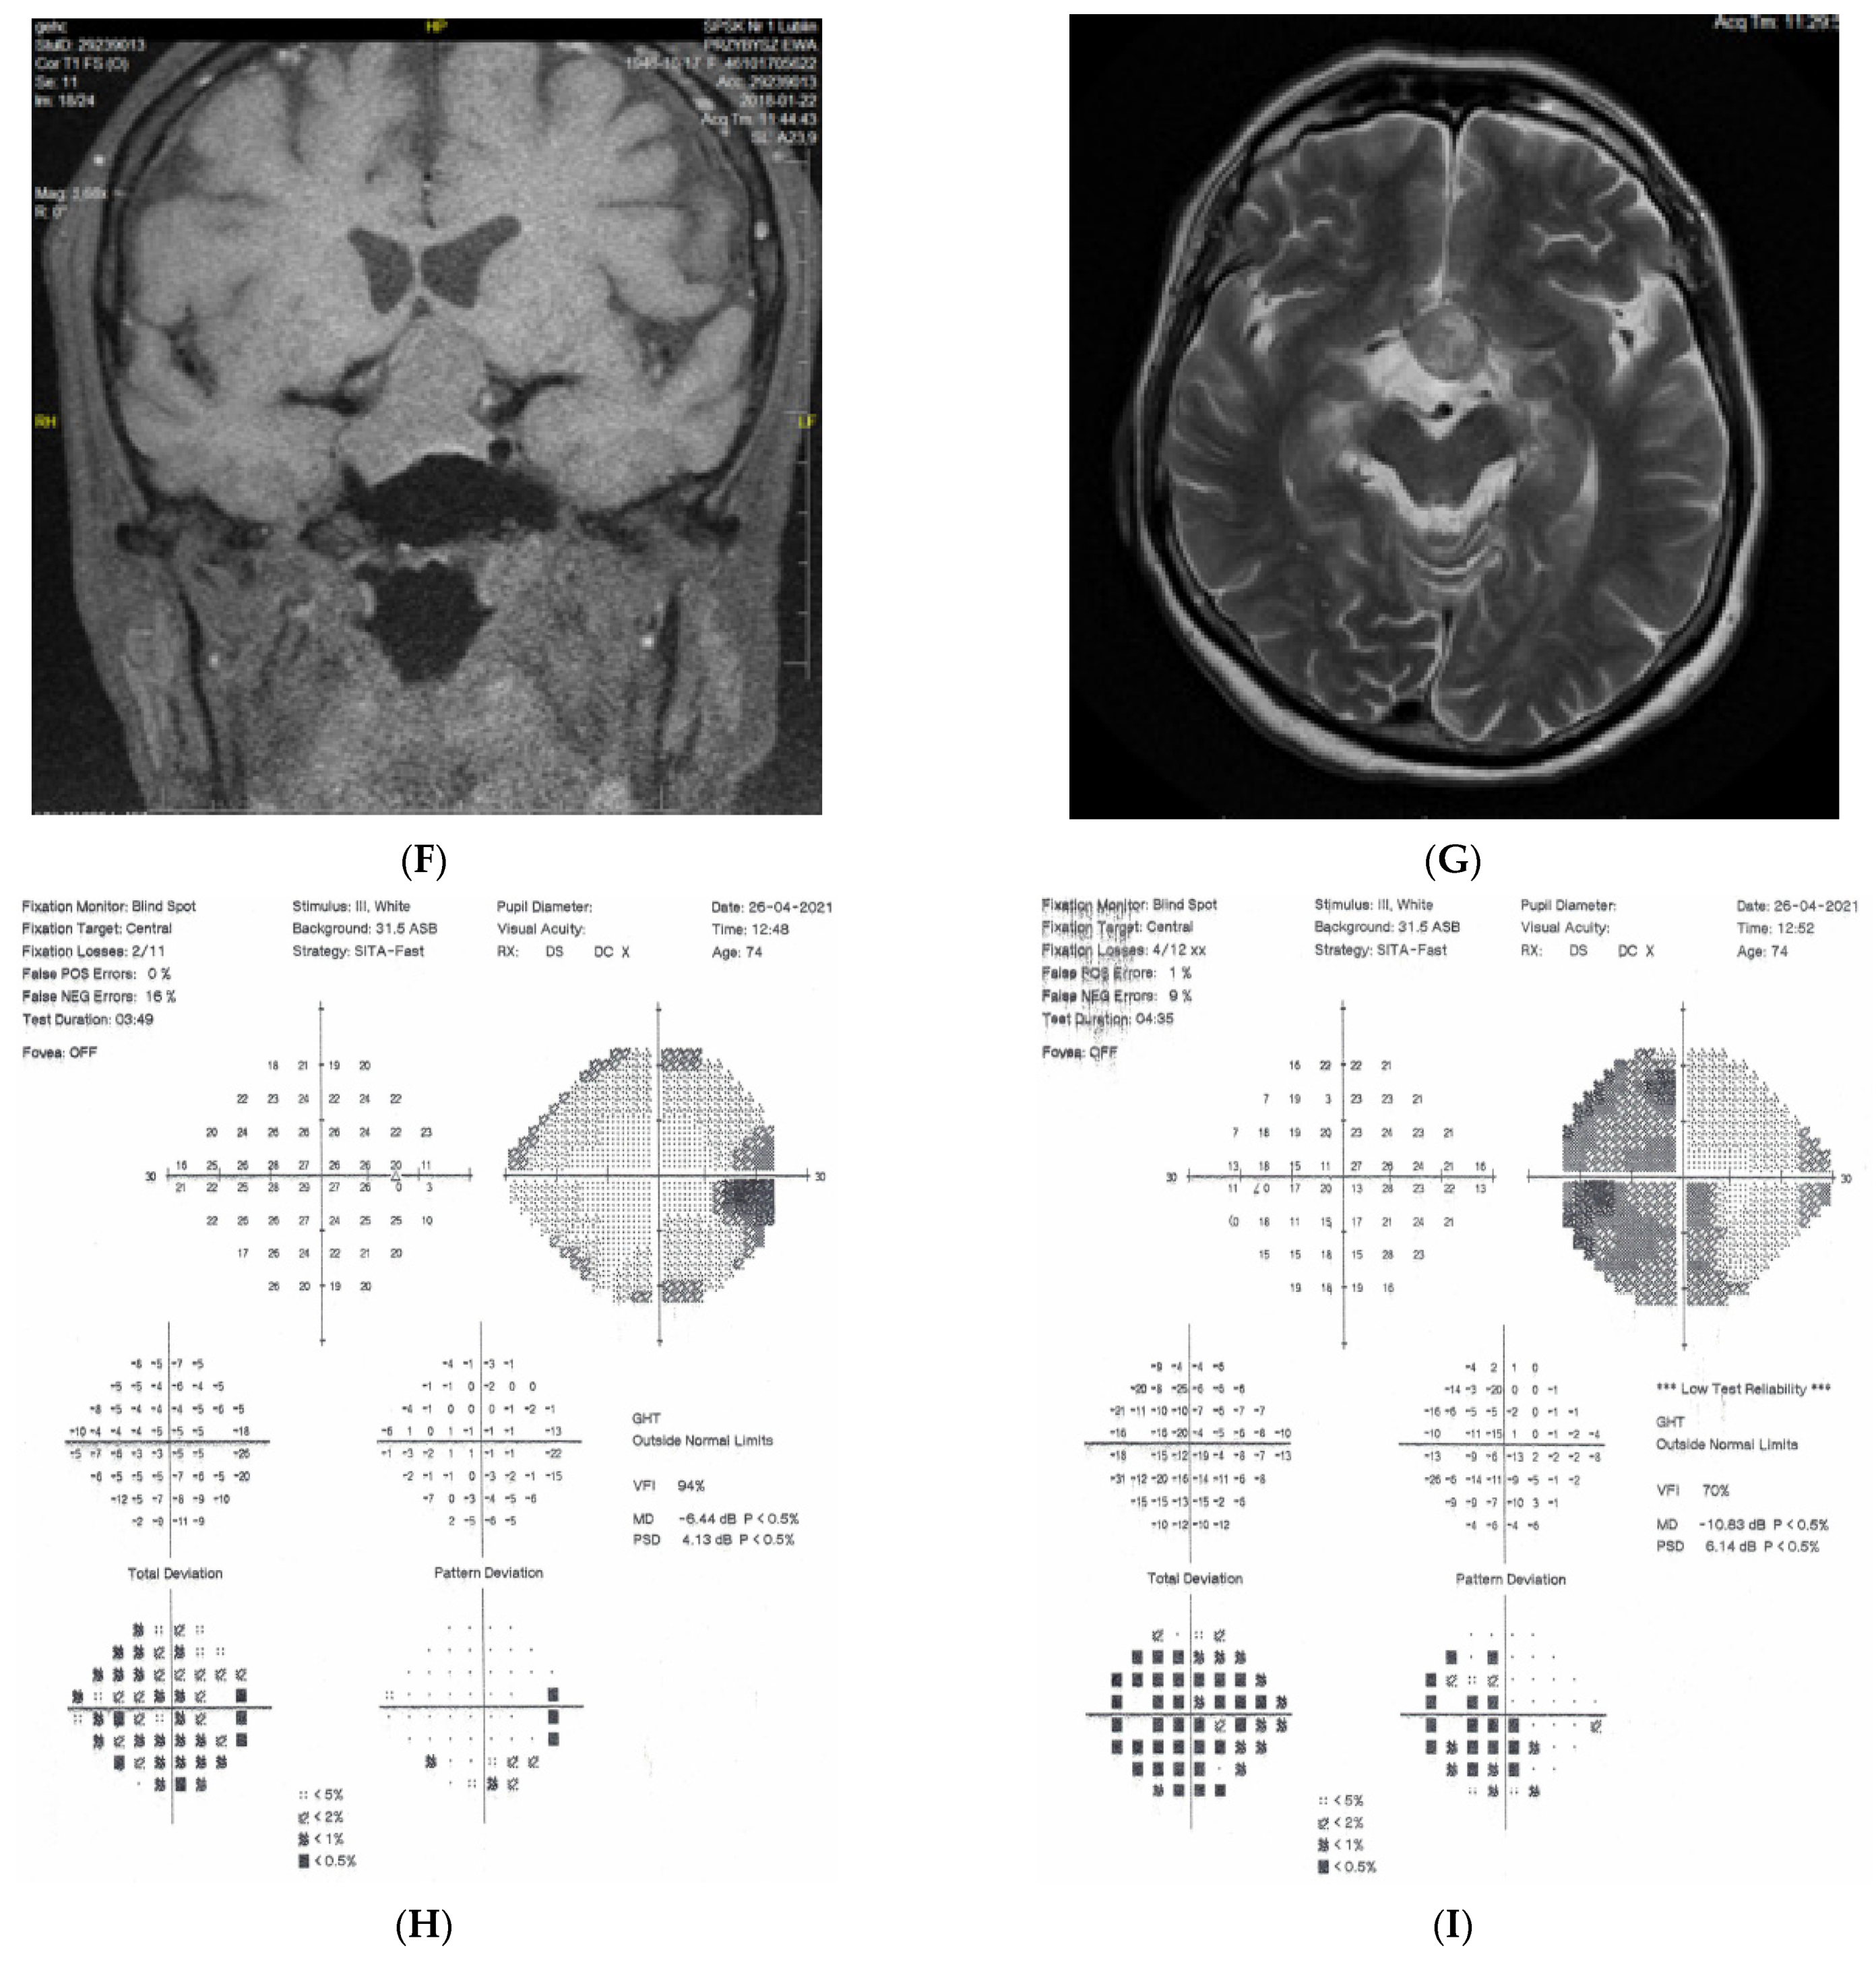

2.1. Case 1

2.2. Case 2